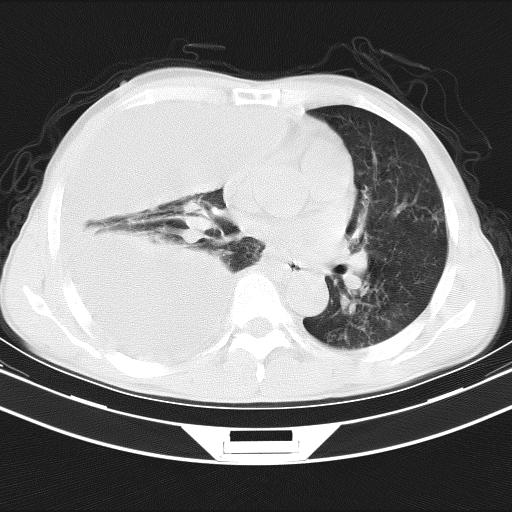

男性,44岁,结核病史多年。现胸闷气短,咳嗽,偶咳血。

右侧胸腔积液

右肺下叶不张

双肺多发结节影最分空洞形成考虑占位不除外结核

双肺陈旧性病变

1、右侧大量胸腔积液伴右肺压缩性膨胀不全,建议抽液治疗后复查 2、两肺继发性tb伴空洞形成。

1)两肺继发性肺结核伴空洞形成,左肺多发性结核球。2)右侧大量胸腔积液伴右肺部分膨胀不全。3)纵隔淋巴结肿大。

吉大一院胸水抽检结果:结核性胸水